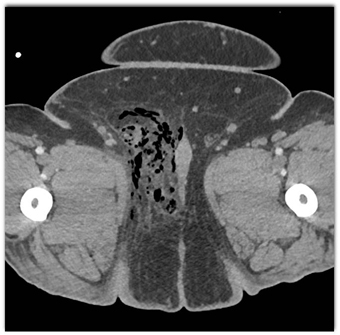

The best diagnosis in this febrile patient is?

rectal perforation

foreign body perforation

necrotizing fasciitis

pelvis abscess